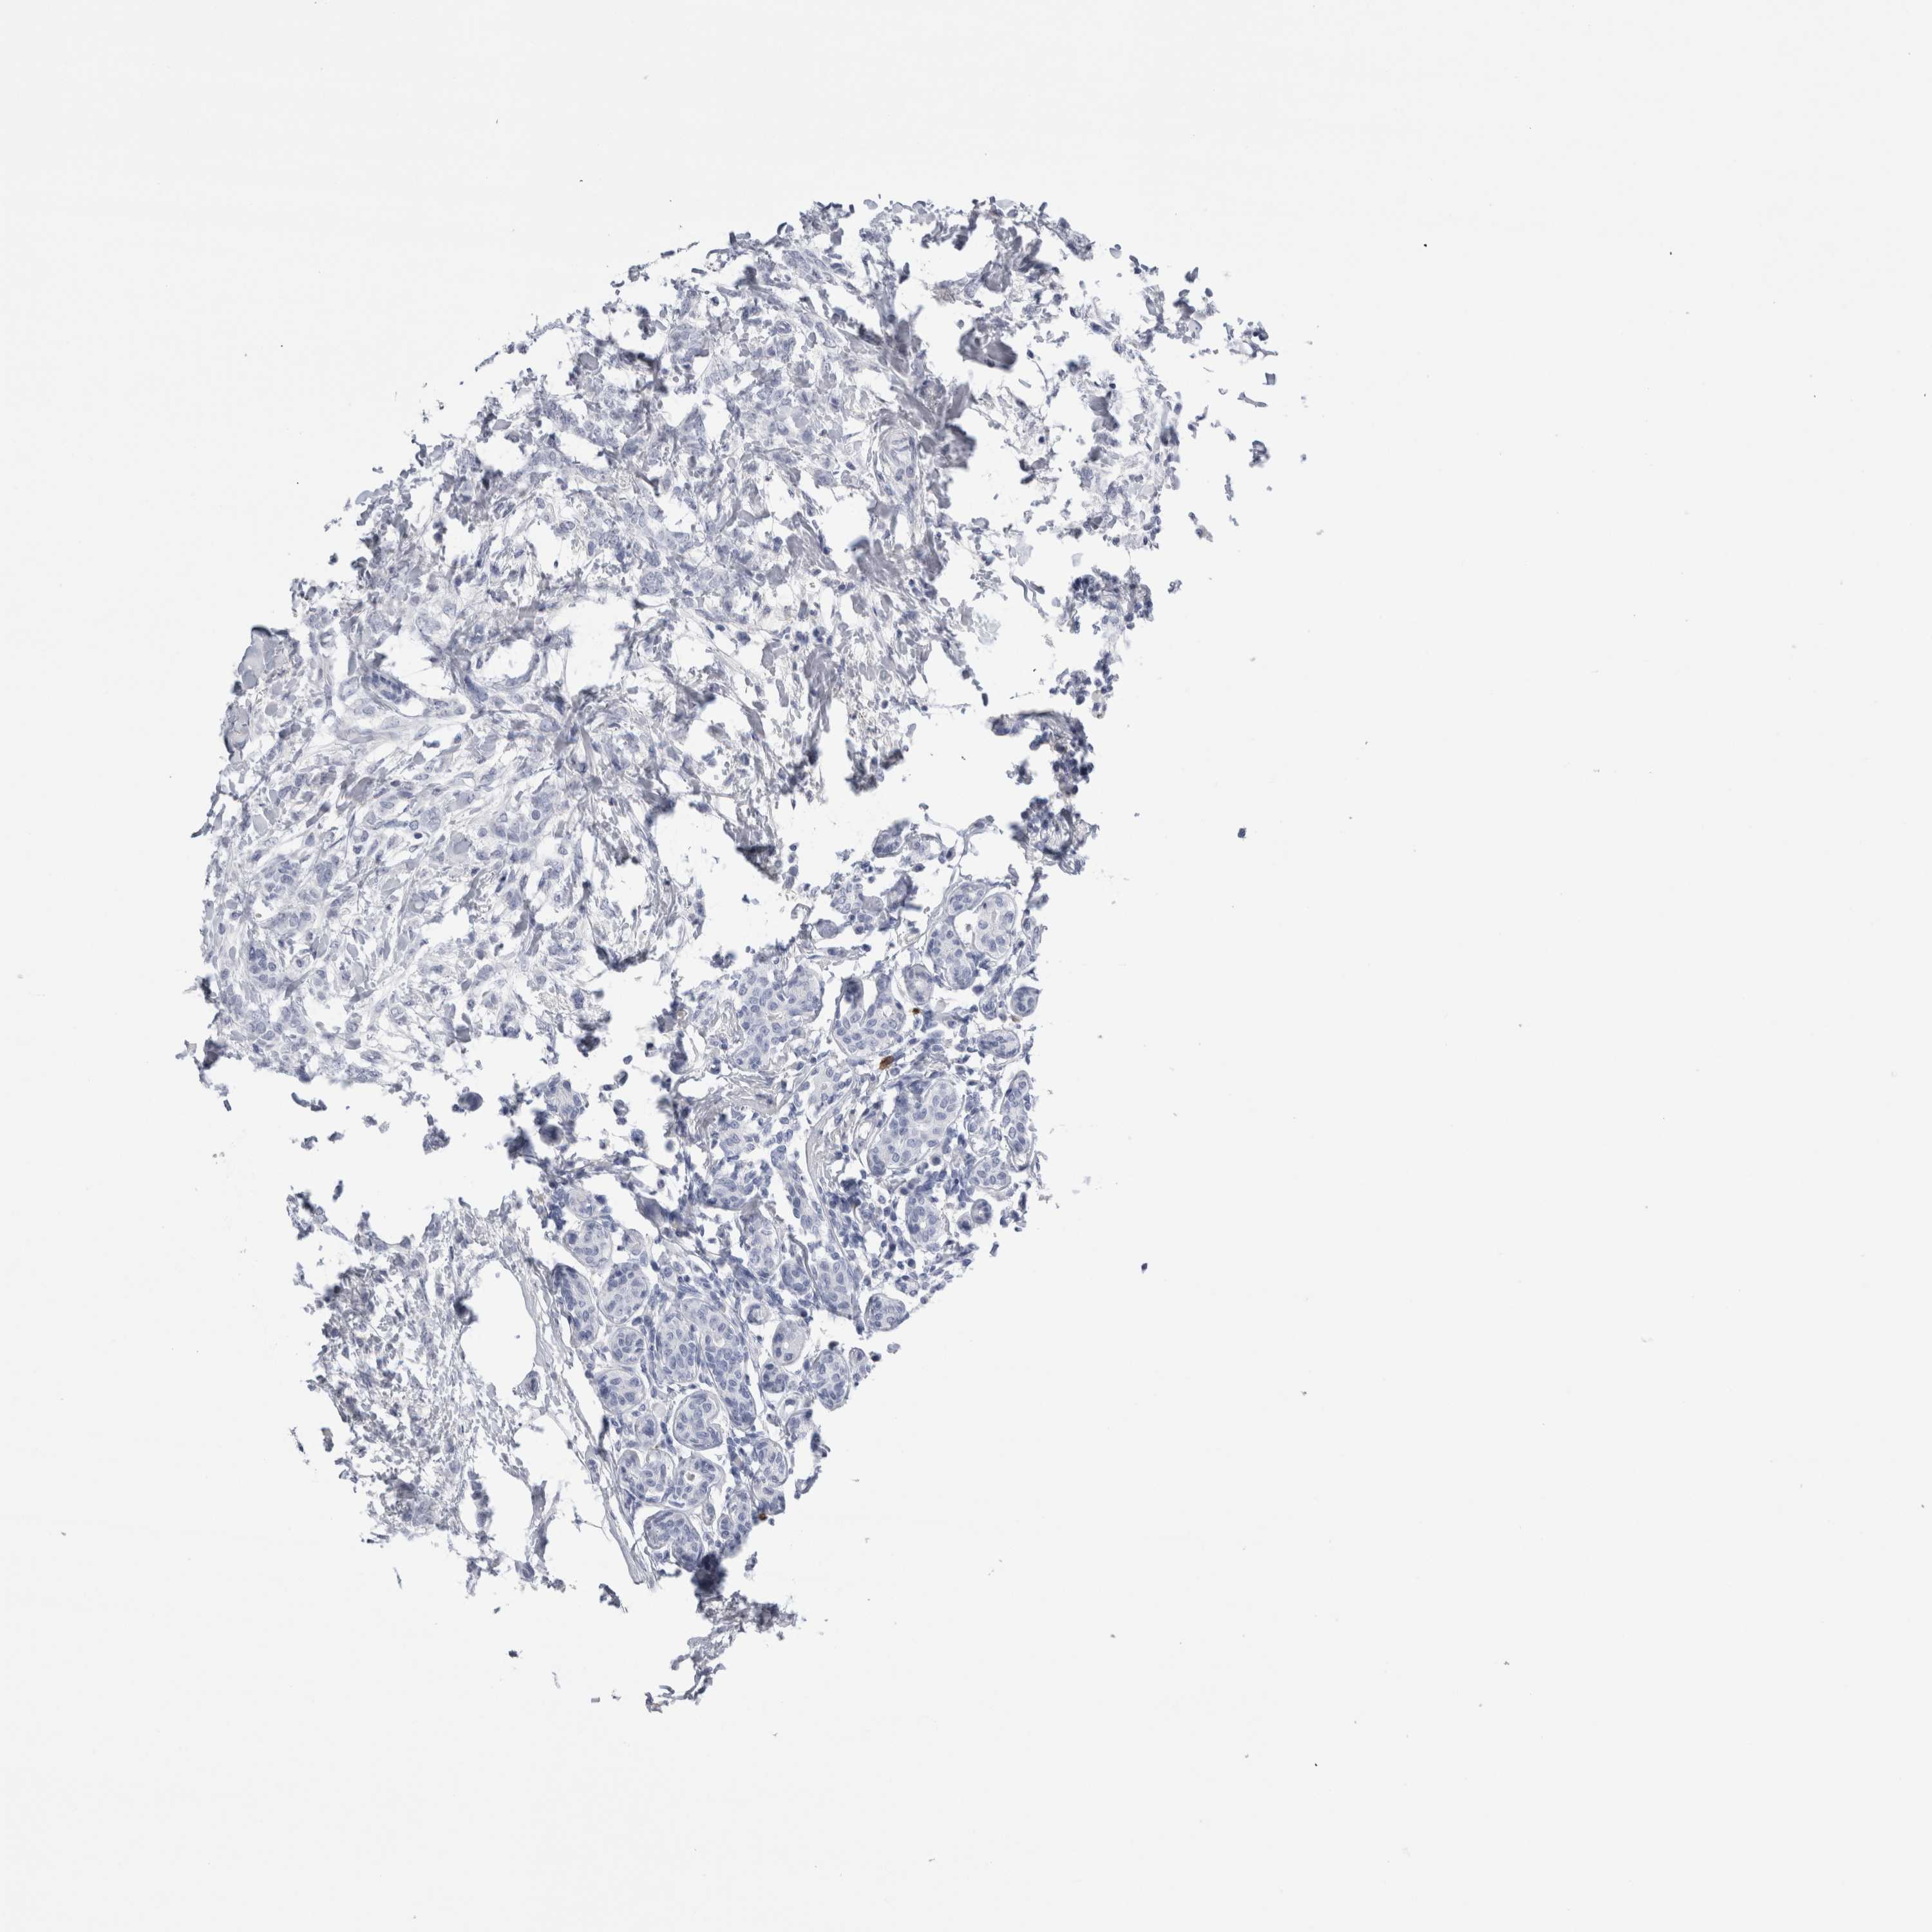

CANCER BREAST CANCER Show tissue menu

Breast cancer

Human cancer

Breast invasive carcinoma